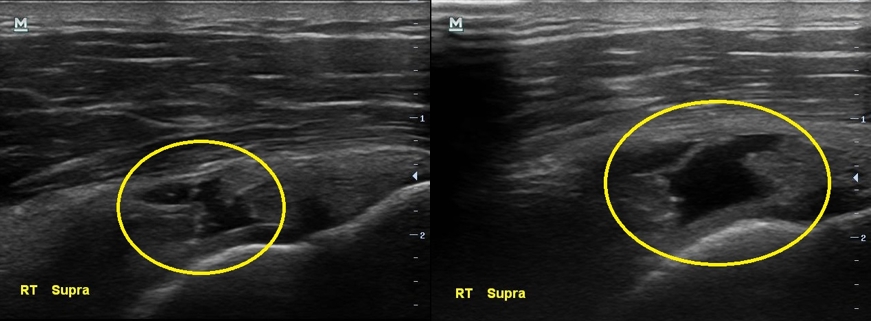

통증이 있지만 운동을 멈추지 않았다는 남자분.... 결과는 생각보다 나빴습니다. 초음파 검사상에서 이두박근의 장두에 염증이 보였고 극상근 힘줄에는 부분파열 소견이 보이고 있었습니다.

초음파 검사 결과 3개월전에 비해 극상근 힘줄의 파열 정도가 더 심해져있습니다.